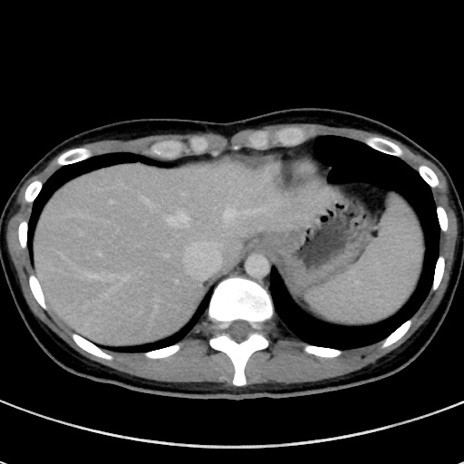

症例17(横断像)

【症例】20歳代女性

【主訴】嘔吐、下腹部痛

【現病歴】昨日夕食後に嘔吐し下腹部痛が出現。本日になっても嘔吐持続し改善しないため来院。

【身体所見】意識清明、BT 37.2℃、BP 108/67mmHg、腹部:平坦、やや硬、下腹部正中から右にかけて圧痛あり、反跳痛軽度あり、tapping pain(+)。

【データ】WBC 13600、CRP 14.94